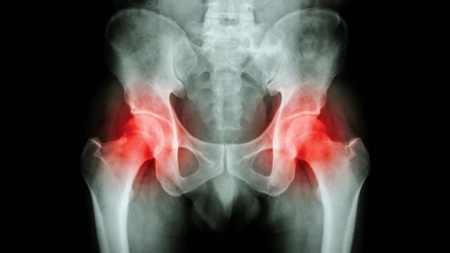

Patients in NHS Grampian benefit from the close working relationship between all specialties involved in the care of musculoskeletal conditions. These include the Department of Rheumatology and the Department of Trauma and Orthopaedic Surgery.